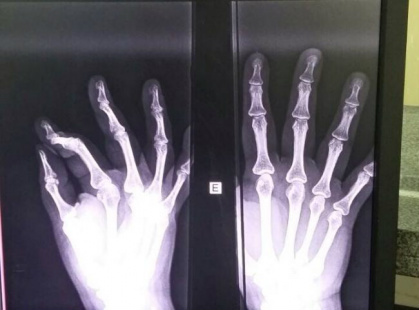

No local, que é de triagem infantil, a mulher jogou um capacete e uma bolsa contra os funcionários. Não contente, a autora então jogou uma garrafa de água contra a porta. Posteriormente ela chutou a mesma porta, na qual a funcionária estava com a mão para fechá-la, momento em que teve o dedo quebrado.

A técnica de enfermagem que terá de ficar afastada do serviço, procurou a delegacia para fazer um boletim de ocorrência. Após os fatos, a autora foi embora da unidade de saúde. Ainda de acordo com funcionários, nenhum guarda municipal apareceu no momento da confusão.“É uma falta de bom senso da prefeitura, fazem esses cortes na saúde e acontece tudo isso”, desabafa um servidor público.